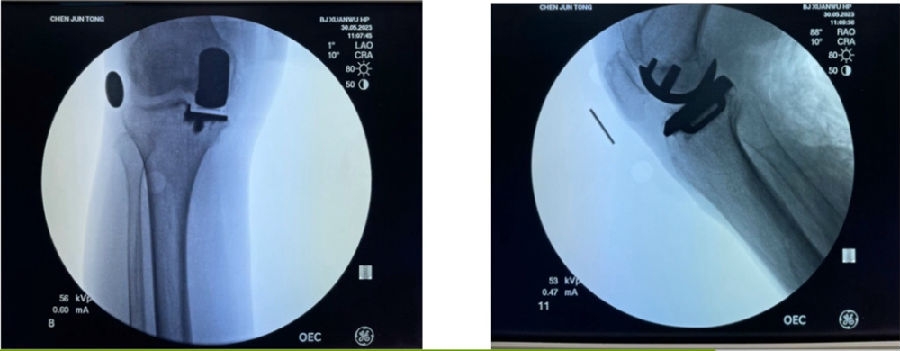

12、术后拍片

目前,笔者团队已经做了70多例,在早期探索过程中可能会出现一些问题,但是之后基本上都是比较好的,术后片子比较赏心悦目。

典型病例